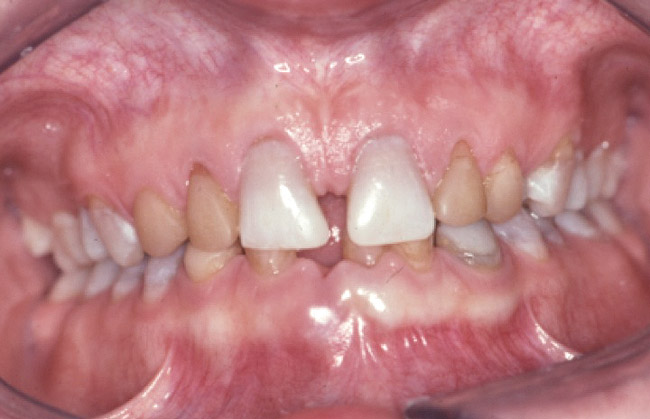

Loss of vertical dimension can be assessed through patient examination intraorally, extraorally, and functionally. Missing teeth and/or teeth worn from clenching or bruxing are the most common intraoral signs of a decreased VDO. Congenitally missing teeth can result in loss of vertical dimension with possible implications of compromised comfort, speech, and chewing (Figure 6 through Figure 8).

Figure 6. The patient is congenitally missing the maxillary lateral incisors and canines and all lower incisors and canines, causing concerns about esthetics. The maxillary laterals and canines and mandibular canines have been bonded with composite.

Figure 6

Figure 7. The mandibular incisors are loose, and No. 25 has recently been lost.

Figure 7

Figure 8. The lower one third of face seems shortened and the upper lip is not well supported and appears thin.

Figure 8